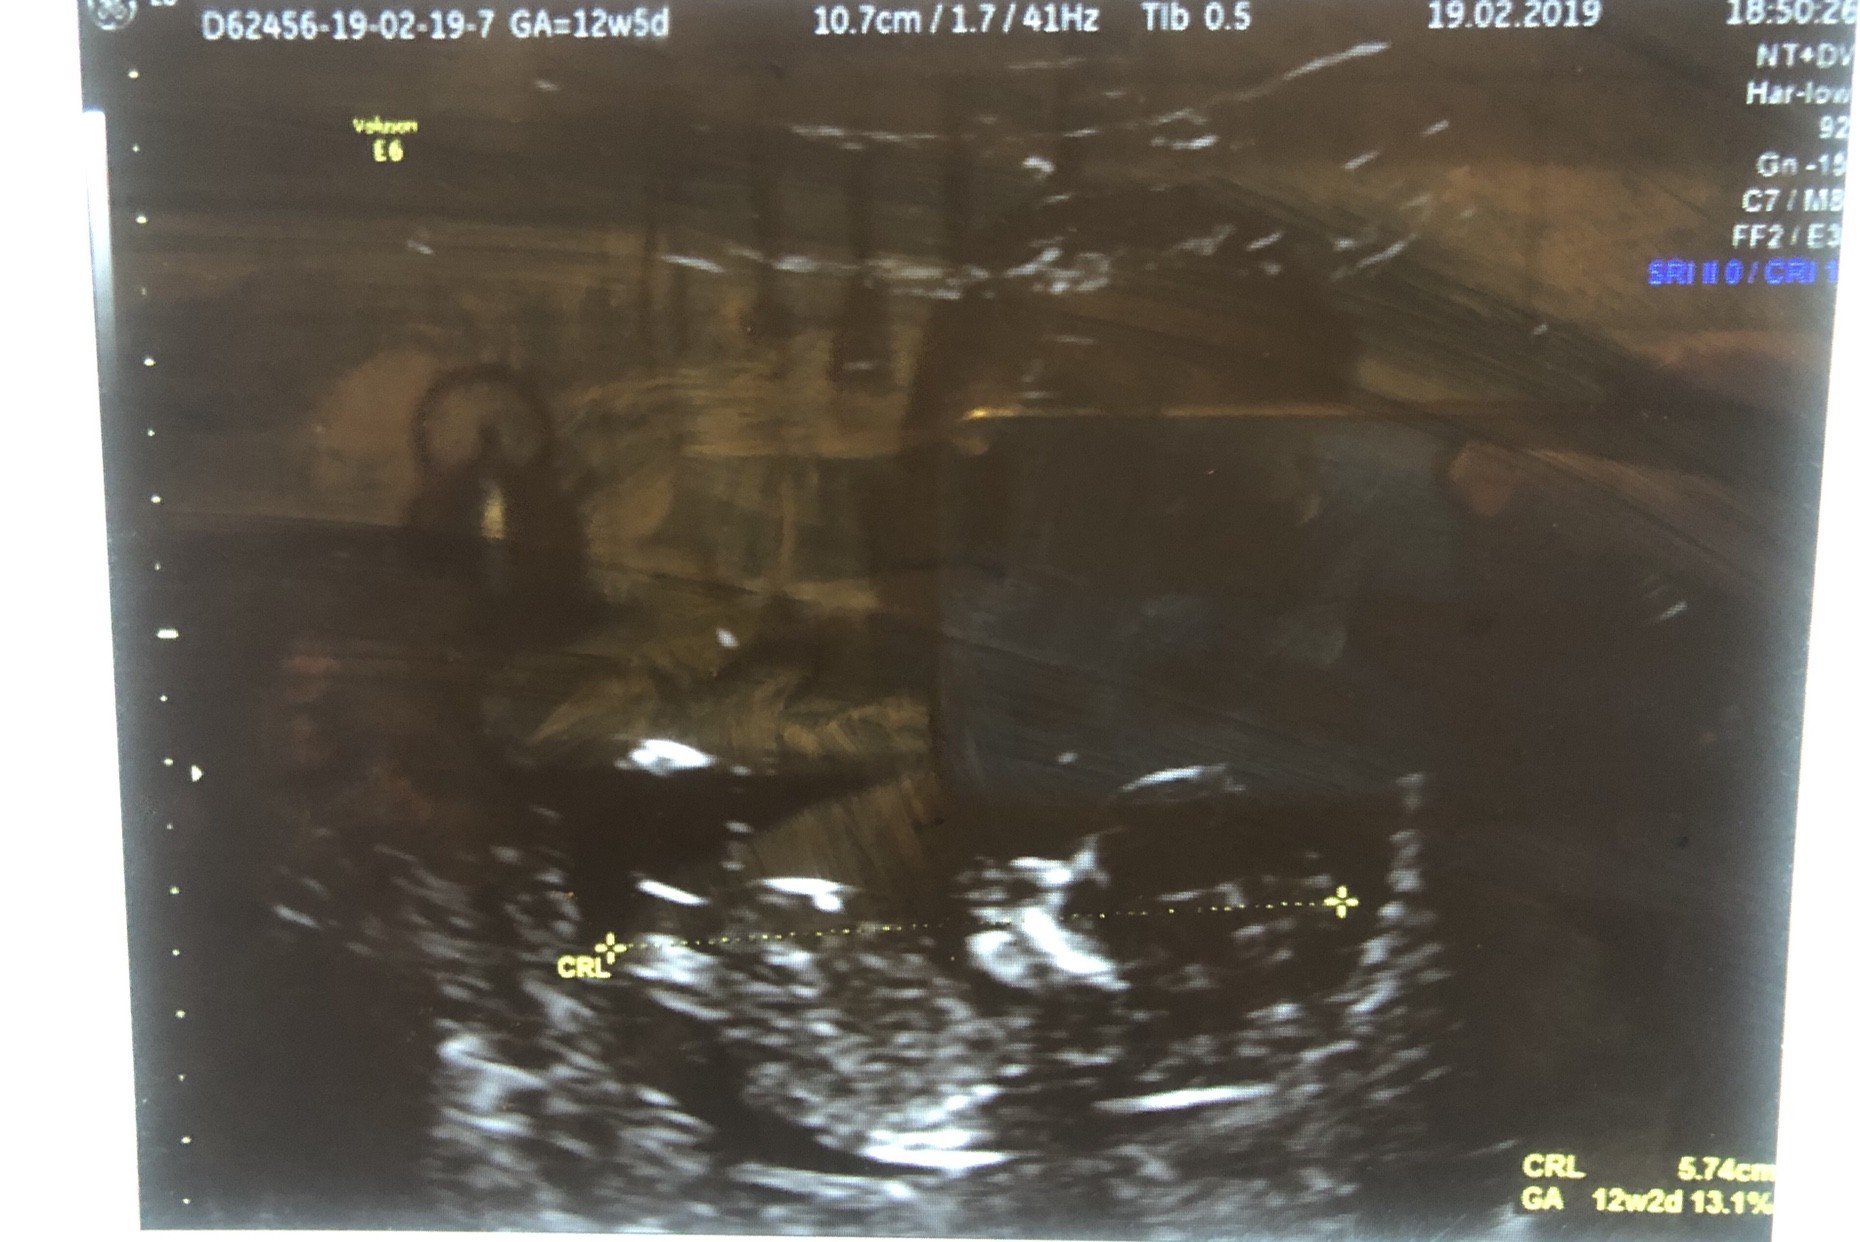

ale cudny widok jak jest jeszcze maluszek w calosci :)